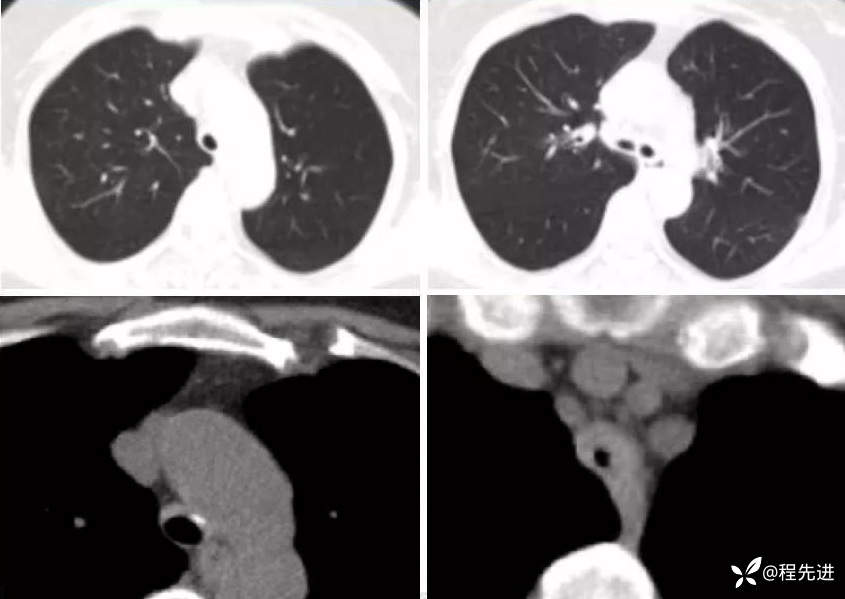

病例一:

患者性别:女

患者年龄:49岁

简要病史:声音嘶哑2年余